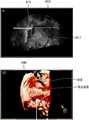

도 8a 및 도 8b는 다른 일부 실시예에 따른, 3 차원 초음파 영상 상에 나타난 디스플레이 볼륨의 깊이가 조절됨에 따라, 초음파 진단 장치(1000)가 디스플레이 볼륨의 표면의 위치를 2 차원 초음파 영상 상에 나타내는 예시를 도시한 도면이다.8A and 8B illustrate a method of adjusting the depth of a display volume displayed on a 3D ultrasound image according to another embodiment of the present invention so that the ultrasound

도 8a를 참조하면, 초음파 진단 장치(1000)는 용종이 발생한 자궁을 나타내는 2 차원 초음파 영상(810)을 디스플레이할 수 있다. 2 차원 초음파 영상(810)은 자궁 내막 및 자궁 내막 아래에 위치한 용종을 나타낼 수 있다.Referring to FIG. 8A, the ultrasound

2 차원 초음파 영상(810) 상에 관심 영역(815)을 설정하는 사용자 입력을 수신함에 따라, 초음파 진단 장치(1000)는, 설정된 관심 영역(815)에 대한 3 차원 초음파 영상(820)을 디스플레이할 수 있다. 3 차원 초음파 영상(820)은 자궁 내막을 표면으로 나타내는 디스플레이 볼륨을 표현할 수 있다. 사용자는 자궁 내막 아래에 위치한 용종을 보기 위해, 초음파 진단 장치(1000)의 사용자 인터페이스를 이용하여 자궁 내막을 깎아낼 수 있다.The ultrasound

도 8b를 참조하면, 3 차원 초음파 영상(820) 상에 나타난 자궁 내막을 깎아내는 사용자 입력을 수신함에 따라, 초음파 진단 장치(1000)는, 자궁 내막을 제거하고, 자궁 내막 내의 용종이 디스플레이 볼륨의 표면으로 표현된 3 차원 초음파 영상(840)을 디스플레이할 수 있다.Referring to FIG. 8B, upon receiving a user input for cutting out the endometrium shown on the

또한, 초음파 진단 장치(1000)는, 2 차원 초음파 영상(810) 상에, 3 차원 초음파 영상(840) 상에 디스플레이된 자궁 용종의 표면의 위치를 나타내는 마커(817)를 디스플레이할 수 있다. 또한, 초음파 진단 장치(1000)는 3 차원 초음파 영상(840) 상에, 2 차원 초음파 영상(810)이 나타내는 대상체의 단면의 위치(845)를 표시할 수 있다.

도 9는 일부 실시예에 따른, 초음파 진단 장치(1000)가, 가상 초음파 내시경 영상이 나타내는 디스플레이 볼륨의 표면의 위치를 2 차원 초음파 영상 상에 나타내는 예시를 도시한 도면이다.9 is a diagram showing an example in which the ultrasonic

도 9를 참조하면, 초음파 진단 장치(1000)는, 3 차원 가상 초음파 내시경 영상(920)이 표현하는 디스플레이 볼륨의 표면의 위치를 2 차원 초음파 영상(910) 상에 표시할 수 있다.9, the ultrasound

초음파 진단 장치(1000)는, 환자의 혈관의 2 차원 초음파 영상(910) 및 환자의 혈관의 2 차원 초음파 영상(910)에 기초하여 생성한 3 차원 가상 초음파 내시경 영상(920)을 디스플레이할 수 있다.The ultrasound

예를 들어, 초음파 진단 장치(1000)는, 3 차원 초음파 영상 그래픽 기술을 이용하여, 2 차원 초음파 영상(910)으로부터 3 차원 가상 초음파 내시경 영상(920)을 생성할 수 있다. 3 차원 초음파 영상 그래픽 기술은 원근 투영 방식을 포함할 수 있으나, 이에 제한되지 않는다. 3 차원 가상 초음파 내시경 방법은 실시예에 따라, 3 차원 가상 초음파 시뮬레이션 방법으로 언급될 수 있다. 3 차원 가상 초음파 내시경 영상(920)을 제공함으로써, 초음파 진단 장치(1000)는, 동맥 내에 실제 내시경을 삽입하여 촬영한 영상과 유사한 영상을 제공할 수 있다.For example, the ultrasound

초음파 진단 장치(1000)는, 2 차원 초음파 영상(910) 상에 가상 카메라의 위치를 나타내는 마커(902), 가상 카메라의 시선 방향 또는 진행 방향을 나타내는 마커(904), 3 차원 가상 초음파 내시경 영상(920)에 디스플레이되고 있는 영역을 나타내는 마커(906), 3 차원 가상 초음파 내시경 영상(920)에서 표현된 표면을 나타내는 라인(908) 및 3 차원 가상 초음파 내시경 영상(920)에서 표현되지 않은 표면을 나타내는 라인(909)을 디스플레이할 수 있다.The ultrasound

초음파 진단 장치(1000)는, 2 차원 초음파 영상(910) 상의 적어도 하나의 지점을 결정할 수 있다. 예를 들어, 초음파 진단 장치(1000)는 동맥(901)의 표면 중 적어도 하나의 지점(912, 914, 916, 918)을 선택하는 사용자 입력을 수신할 수 있다.The ultrasound

적어도 하나의 지점을 결정함에 따라, 초음파 진단 장치(1000)는, 2 차원 초음파 영상(910) 상의 결정된 지점에 대응되는 3 차원 가상 초음파 내시경 영상(920) 상의 지점을 결정할 수 있다.The ultrasound

예를 들어, 초음파 진단 장치(1000)는, 동맥(901)의 표면 중 제 1 지점(912)이 3 차원 가상 초음파 내시경 영상(920) 상의 제 1 지점(922)에, 동맥(901)의 표면 중 제 2 지점(914)이 3 차원 가상 초음파 내시경 영상(920) 상의 제 2 지점(924)에, 동맥(901)의 표면 중 제 3 지점(916)이 3 차원 가상 초음파 내시경 영상(920) 상의 제 4 지점(926)에, 동맥(901)의 표면 중 제 4 지점(918)이 3 차원 가상 초음파 내시경 영상(920) 상의 제 4 지점(928)에 대응되는 것으로 결정할 수 있다.For example, the ultrasound

초음파 진단 장치(1000)는, 2 차원 초음파 영상(910) 상의 지점에 대응되는 3 차원 가상 초음파 내시경 영상(920) 상의 지점 상에, 대응되는 지점임을 나타내는 마커를 디스플레이할 수 있다.The ultrasound

또한, 초음파 진단 장치(1000)는, 가상 카메라의 위치(902)로부터 동일한 거리에 있는 지점들의 위치를 3 차원 가상 초음파 내시경 영상(920) 상에 디스플레이할 수 있다. 예를 들어, 초음파 진단 장치(1000)는, 가상 카메라의 위치(902)로부터 동일한 거리에 있는 지점들을 잇는 선(934, 936, 938)을 3 차원 가상 초음파 내시경 영상(920) 상에 디스플레이할 수 있다.Further, the ultrasound

또한, 초음파 진단 장치(1000)는, 3 차원 가상 초음파 내시경 영상(920) 상의 지점을 선택하는 사용자 입력을 수신하고, 선택된 지점에 대응되는 2 차원 초음파 영상(910) 상의 지점의 위치를 2 차원 초음파 영상(910) 상에 디스플레이할 수도 있다.The ultrasound

이에 따라, 사용자는, 2 차원 초음파 영상(910)에서 확인된 관심 부위를 3 차원 가상 초음파 내시경 영상(920)으로 보고자 할 때, 가상 카메라의 시점의 위치와 시선 방향을 용이하게 조절할 수 있다.